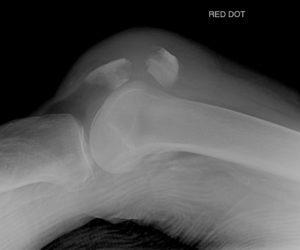

Диагностика

Диагностика перелома коленной чашечки, определение симптомов и назначение терапии осуществляется в стационарных условиях на основе клинической картины. Травматолог выполняет рентгенографию. Для получения более детальной информации пациента направляют на МРТ колена, а также выполняется пункция сустава.

При установлении диагноза крайне важно точно оценить степень повреждения сустава и исключить разрывы связок надколенника или сухожилий, травматический артрит и другие заболевания.